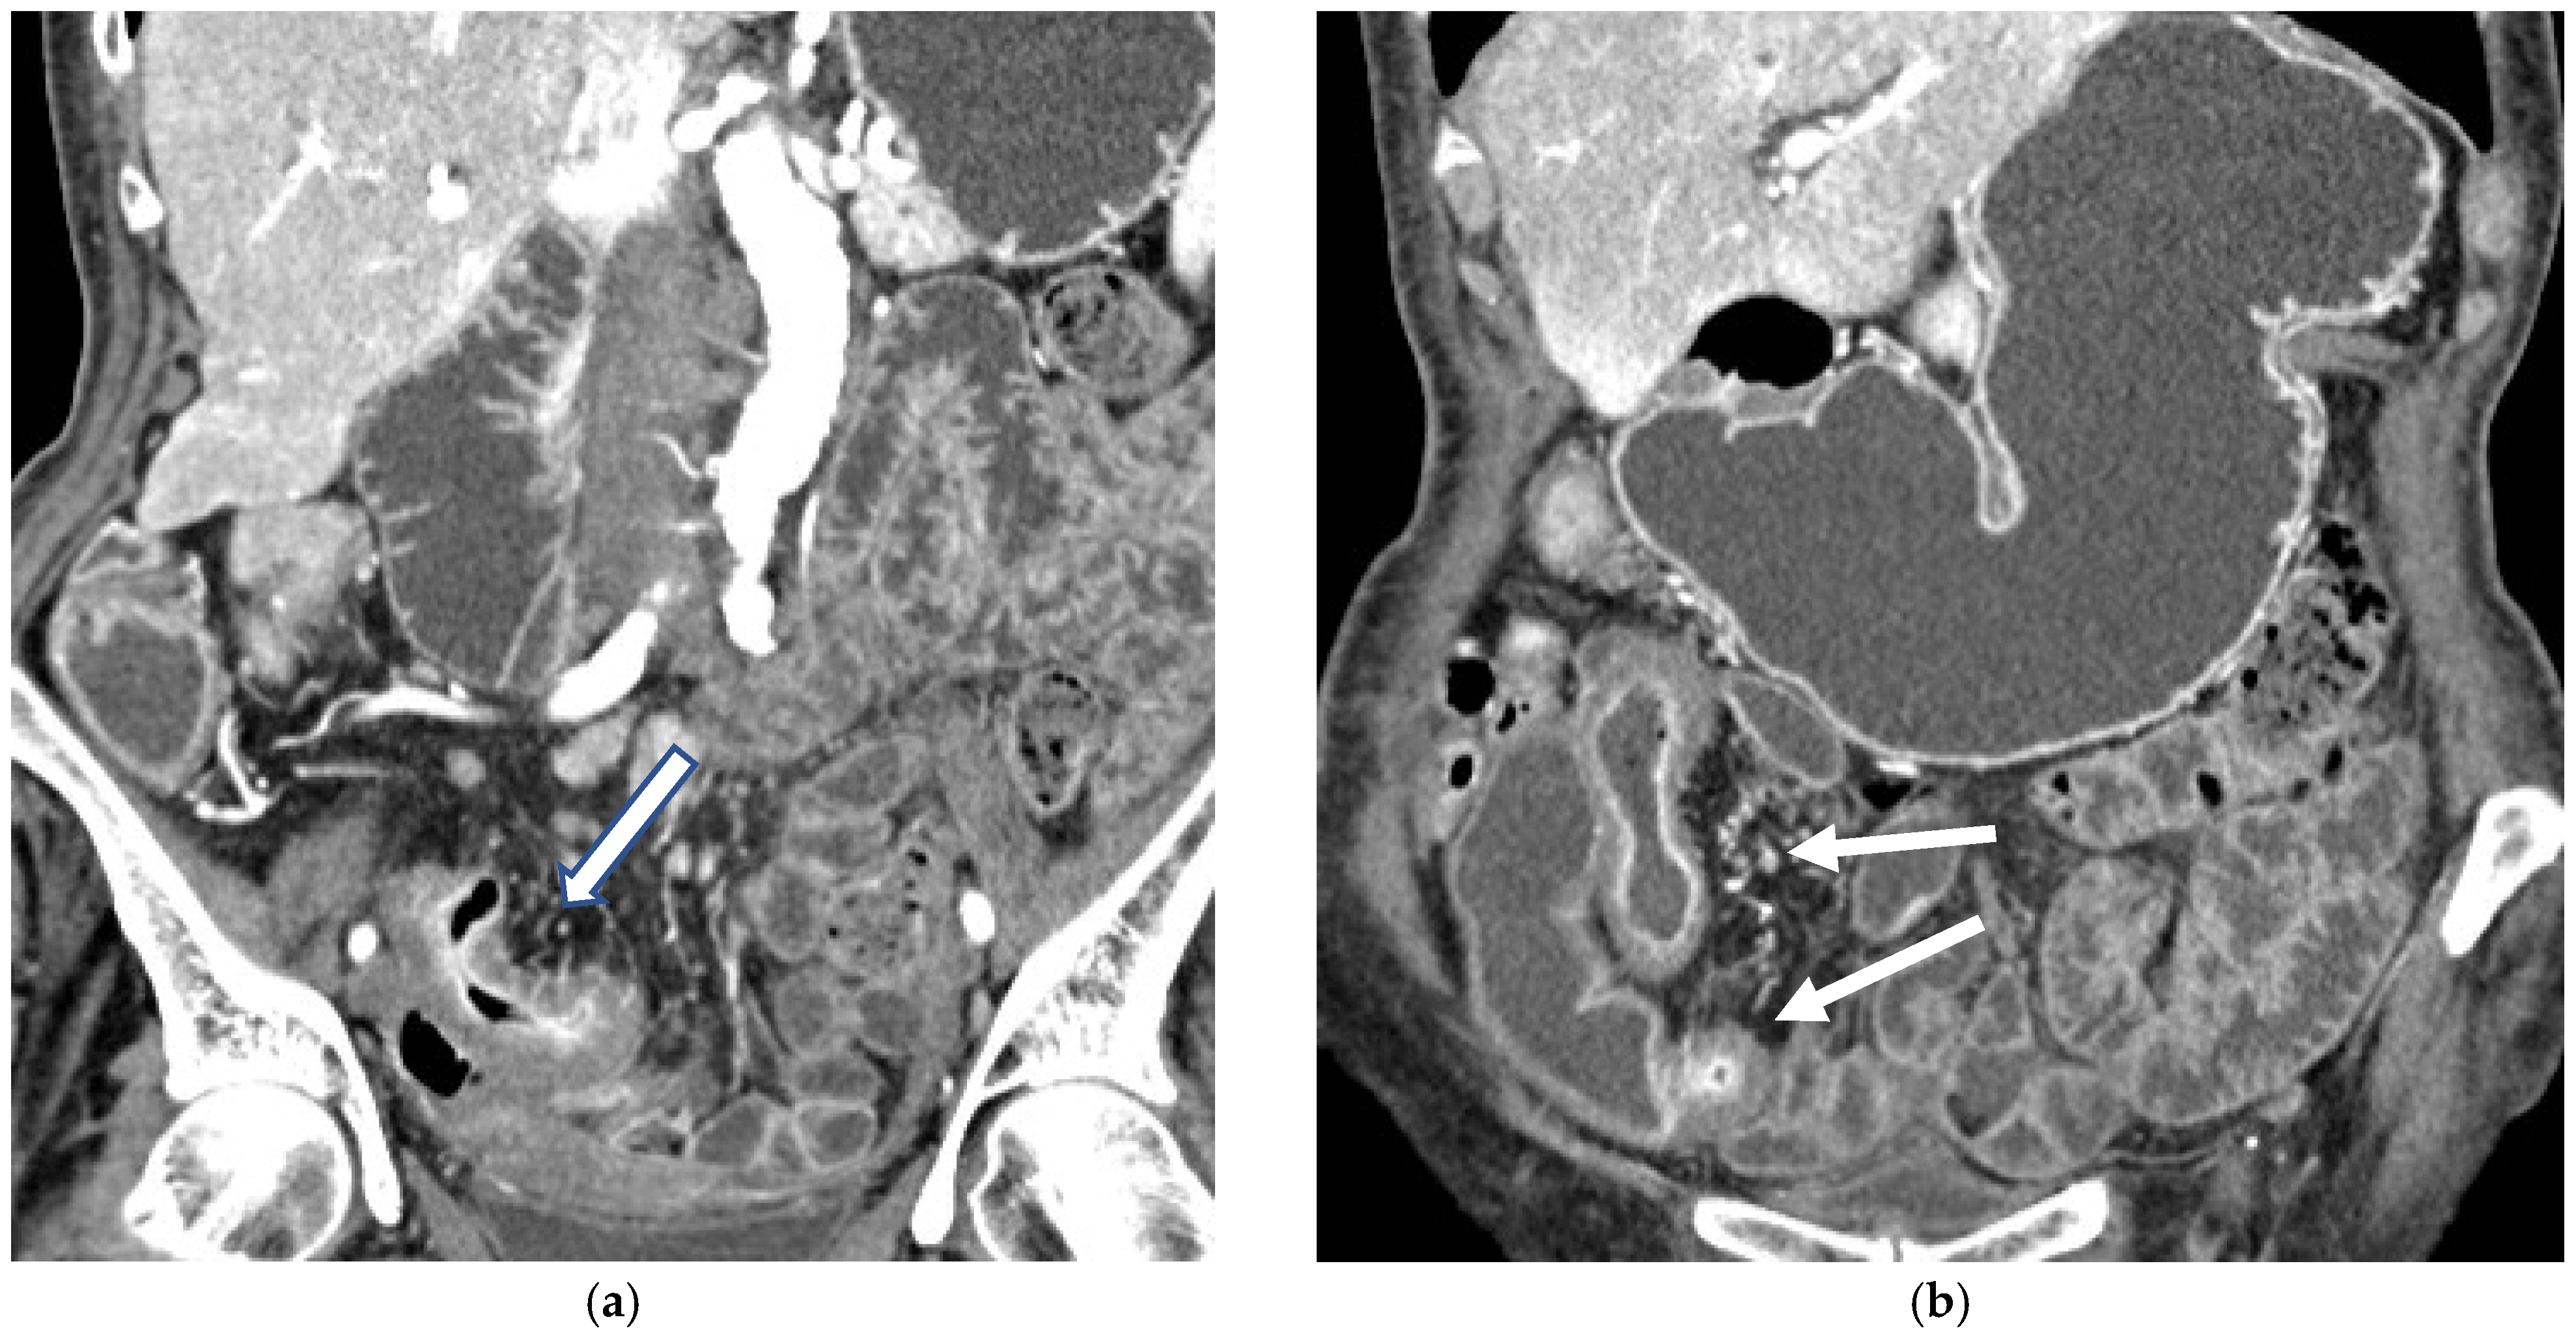

CT Enterography (CTE) is a dedicated technique that can be performed using either neutral (water macrogol solutions) or positive (iodinated) oral contrast for optimal luminal distention, thereby enhancing the modality’s utility in elective outpatient evaluation, shown on Figure 4 and Figure 5. CTE performed with positive oral contrast improves visualization of the entire small bowel lumen and interloop relationships, and is particularly useful in complex disease associated with adhesions and fistulas (Figure 4a–d and Figure 5a–d). On the other hand, CTE performed with negative oral contrast enables assessment of mucosal hyper-enhancement, wall thickening, and inflammatory changes (Figure 5). However, although CTE can approximate much of the mural and extramural information obtained with MRE, it lacks the functional imaging capabilities of MRI and cannot distinguish with confidence between inflammatory and fibrotic strictures. For this reason, CT is generally reserved for situations in which MRE is unavailable or contraindicated, or when specific luminal abnormalities, such as unexplained focal thickening or suspected small-bowel polyps, require rapid clarification [20,21,39,40,41].

Figure 5.

(a,b) Coronal CT scan in the venous phase after administration of negative oral contrast medium (PEG-solution) showing thickened ileal loops (arrows) in an 85-year-old female patient with Crohn’s disease. (c,d) axial CT scan in the venous phase after administration of negative oral contrast medium (PEG-solution) showing thickened ileal loop (arrows) in an 85-year-old female patient with Crohn’s disease.